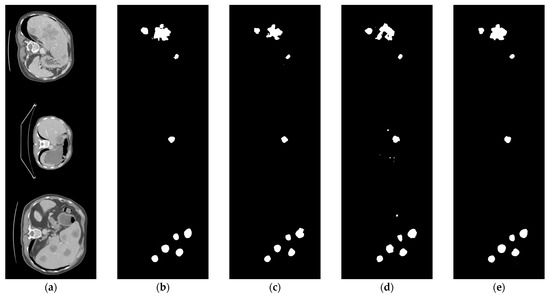

5.1. Dataset

5.2. Data Preprocessing

5.3. Experiments